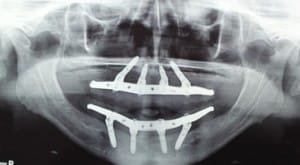

IMPLANTOLOGIA ORAL

CIRUGÍA MAXILOFACIAL

santiago-gonzalez-implantes-12